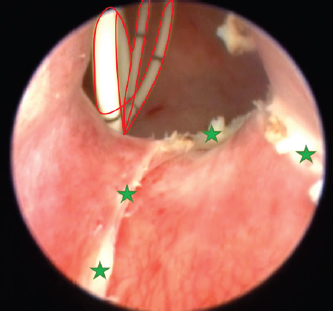

The surgery aimed to cut the outer ureteral membrane and redirect left kidney-produced urine from the urethra to the bladder. Before cutting, a hydrophilic 3 Fr catheter was introduced through a pathologic left ureter opening. It worked as a guide to fully visualize the intramural ureteral tunnel. After that, a Karl Storz monopolar coagulating ball electrode (3 Fr × 53 cm) was introduced through the working channel of the cystoscope sheath. The electrode cut the medial aspect of the ureteral wall up to the bladder trigone, where the contralateral normal ureter opens. The cut membrane did not bleed during the surgery (Figs. 68).

Fig. 6. Cystoscopy picture where the ureteral membrane (see the green stars) is seen before cutting with the semirigid Karl Storz monopolar coagulating ball electrode (marked with a red arrow). A bright yellow 3 Fr guide catheter is seen on the right side of the picture (marked with a yellow arrow).